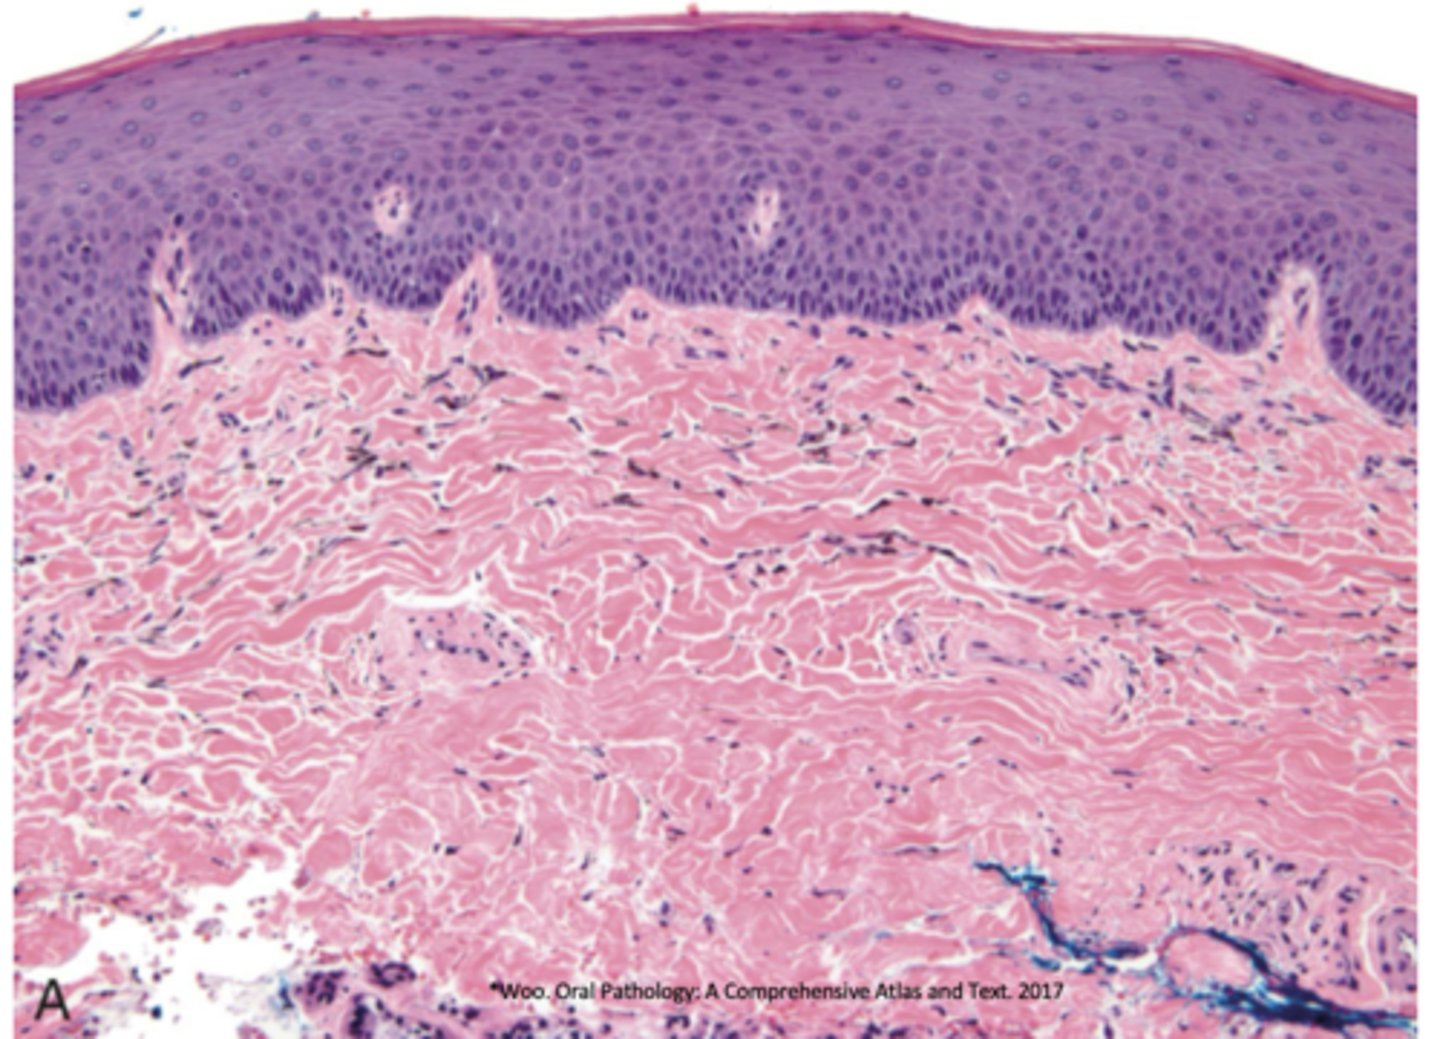

What pigmented lesion has these histopathologic features?

- Dendritic melanocytes throughout epithelium

- Thickened epithelium

- Increase in basal layer melanocytes

- Spongiosis and mild acanthosis

oral melanoacanthosis

What is the treatment of oral melanoacanthosis?

- Biopsy to r/o melanoma

- No further rx required